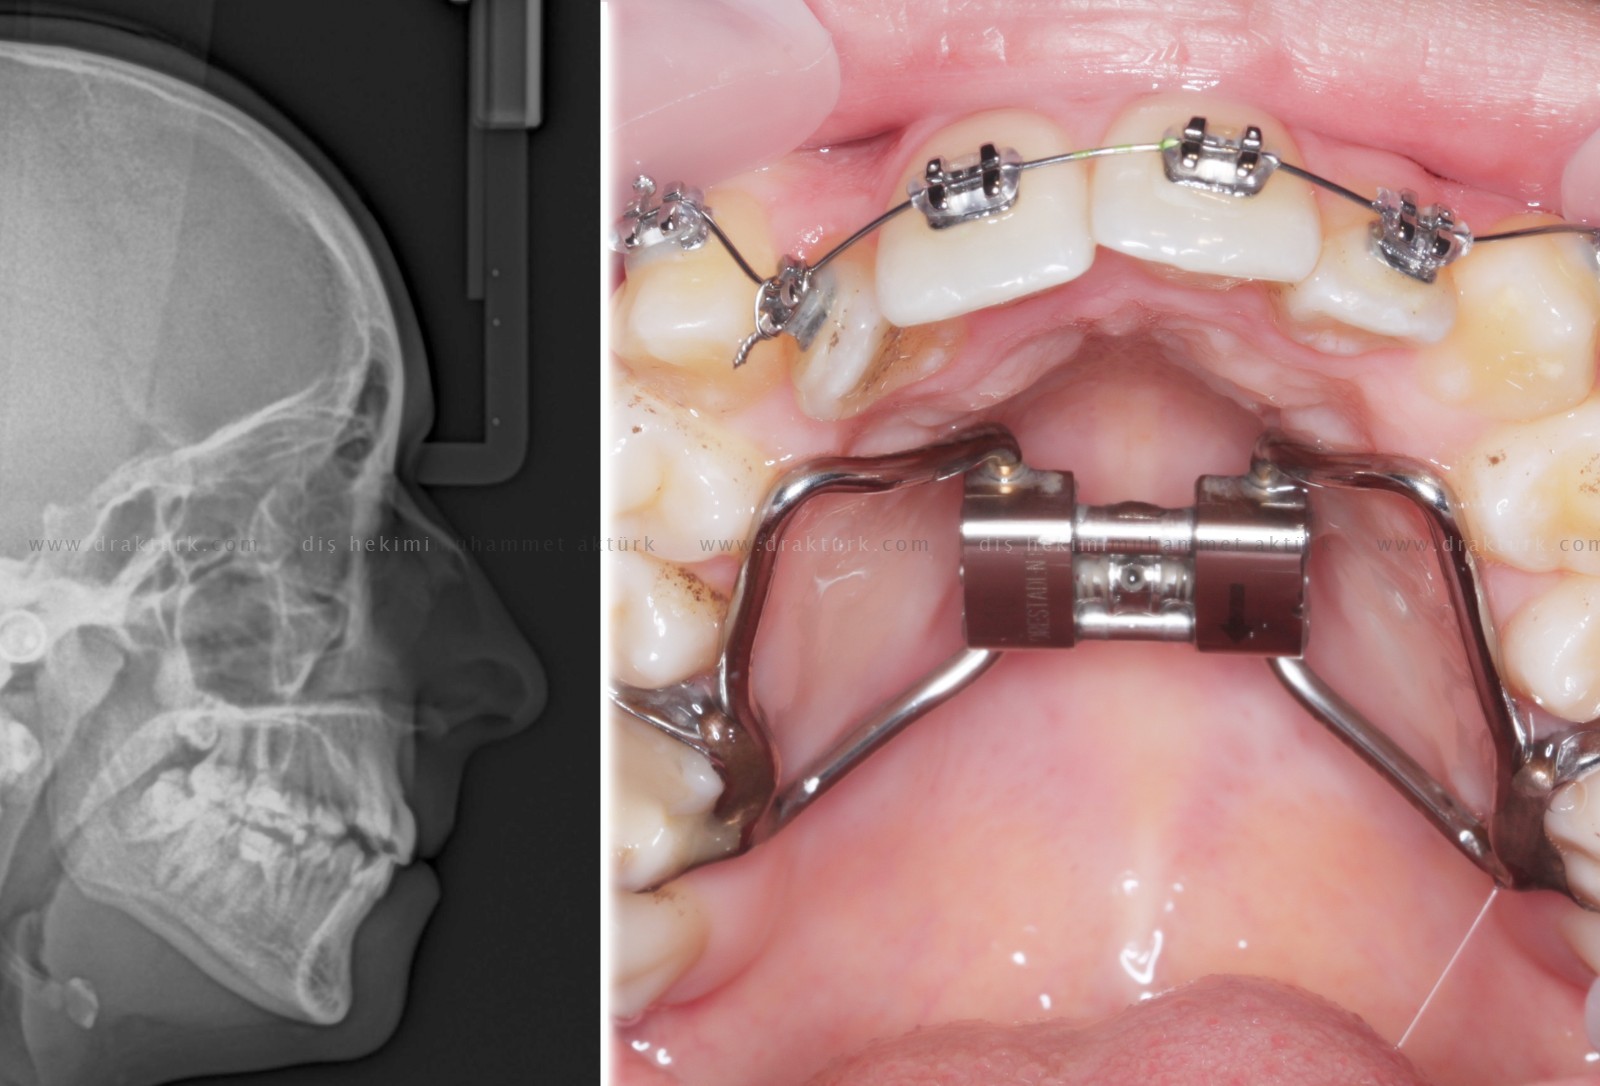

An example of the treatments we have done :

TREATMENT of ANTERIOR TOOTH FRACTURE WITH AESTHETIC COMPOSITE FILLING